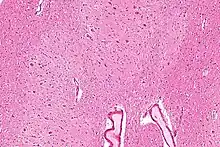

The dentate nucleus is a cluster of neurons, or nerve cells, in the central nervous system that has a dentate – tooth-like or serrated – edge. It is located within the deep white matter of each cerebellar hemisphere, and it is the largest single structure linking the cerebellum to the rest of the brain.[1] It is the largest and most lateral, or farthest from the midline, of the four pairs of deep cerebellar nuclei, the others being the globose and emboliform nuclei, which together are referred to as the interposed nucleus, and the fastigial nucleus. The dentate nucleus is responsible for the planning, initiation and control of voluntary movements. The dorsal region of the dentate nucleus contains output channels involved in motor function, which is the movement of skeletal muscle, while the ventral region contains output channels involved in nonmotor function, such as conscious thought and visuospatial function.

Location

The architecture of cerebellum has a form that resembles the structure of a crystal, so a slice anywhere in the cerebellum gives repeated architecture. The eight cerebellar nuclei, located within the deep white matter of each cerebellar hemisphere, are grouped into pairs, with one of each pair in each of the two hemispheres. As a chunk of tissue, the dentate nucleus with overlying cerebellar cortex makes up a functional unit called the cerebrocerebellum. Thus, there is a part of cerebellum that communicates exclusively with the dentate nucleus.[4]

Morphology